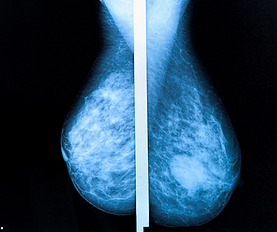

Mastografía y estudios mamarios:

Información que sí se entiende

Traducimos términos médicos como BI-RADS, mastografía o ultrasonido a un lenguaje claro y útil.

Mastografía

Cuándo se recomienda y cada cuánto realizarla

Ultrasonido mamario

En qué casos se utiliza